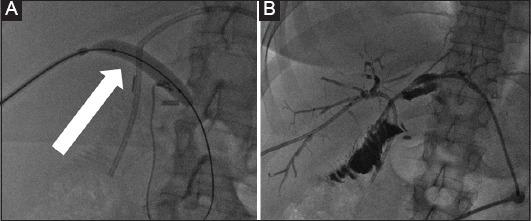

Gallstones are primarily crystalline cholesterol formations that may present significant medical concerns, often leading to bile duct obstruction. Their genesis is multifaceted, influenced by genetics, diet and age. Over the decades, the biliary stone management domain has undergone a transformation, propelled by clinical demands and technological advances. This review focuses on percutaneous treatments, highlighting the shift from foundational percutaneous transhepatic cholangiography to advanced percutaneous transhepatic cholangioscopy, emphasizing patient safety, efficacy, and outcomes. The significance of patient-reported outcomes, capturing aspects that include pain and post-intervention quality of life, is accentuated. A critical analysis reveals a gap in our understanding of the long-term resilience of percutaneous interventions, particularly with respect to averting stone recurrence or treating chronic strictures. The potential of technological enhancements, including advanced endoscopes and real-time imaging, is acknowledged, though the need for rigorous clinical validation must be stressed. Decision-making challenges, due to the myriads of available interventions, are highlighted, emphasizing the need for evidence-based algorithms. Economically, the cost dynamics, both direct and ancillary, of these interventions come to the forefront. Concluding, the paper advocates for continuous innovation, ensuring that biliary stone management remains efficient, patient-centered, safe, and economically justified.

胆结石主要是结晶性胆固醇形成物,可能引发重大医学问题,常导致胆管阻塞。其成因是多方面的,受遗传、饮食和年龄影响。几十年来,受临床需求和技术进步推动,胆管结石治疗领域发生了变革。本综述聚焦于经皮治疗,突出了从基础经皮肝穿刺胆管造影到先进经皮肝穿刺胆管镜检查的转变,强调了患者安全、疗效和治疗结果。强调了患者报告结果的重要性,涵盖疼痛和干预后生活质量等方面。批判性分析表明,我们对经皮干预的长期恢复力认识存在差距,尤其是在预防结石复发或治疗慢性狭窄方面。尽管必须强调需要严格的临床验证,但也承认包括先进内窥镜和实时成像在内的技术改进的潜力。由于可用干预措施众多,突出了决策挑战,强调了基于证据的算法的必要性。在经济方面,这些干预措施的直接和间接成本动态成为首要问题。总之,本文倡导持续创新,确保胆管结石治疗保持高效、以患者为中心、安全且在经济上合理。